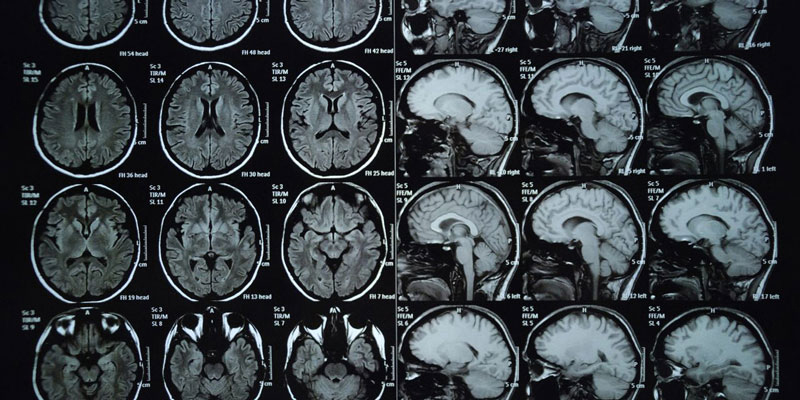

Bệnh não mô cầu do vi khuẩn Neisseria meningitidis gây ra, có hơn 12 nhóm huyết thanh, trong đó các nhóm A, B, C, W, Y thường gây bệnh ở người. Bệnh có thể xuất hiện rải rác quanh năm, nhưng thường bùng phát thành ổ dịch nhỏ vào mùa đông – xuân khi thời tiết lạnh và ẩm. Trẻ em và thanh thiếu niên là nhóm dễ mắc nhất do hệ miễn dịch còn yếu hoặc sinh hoạt tập trung trong trường học, ký túc xá. Tỷ lệ tử vong cao (có thể lên đến 50% nếu không được điều trị kịp thời) và nhiều trường hợp để lại di chứng nặng nề như điếc, tổn thương não, hoại tử chi.